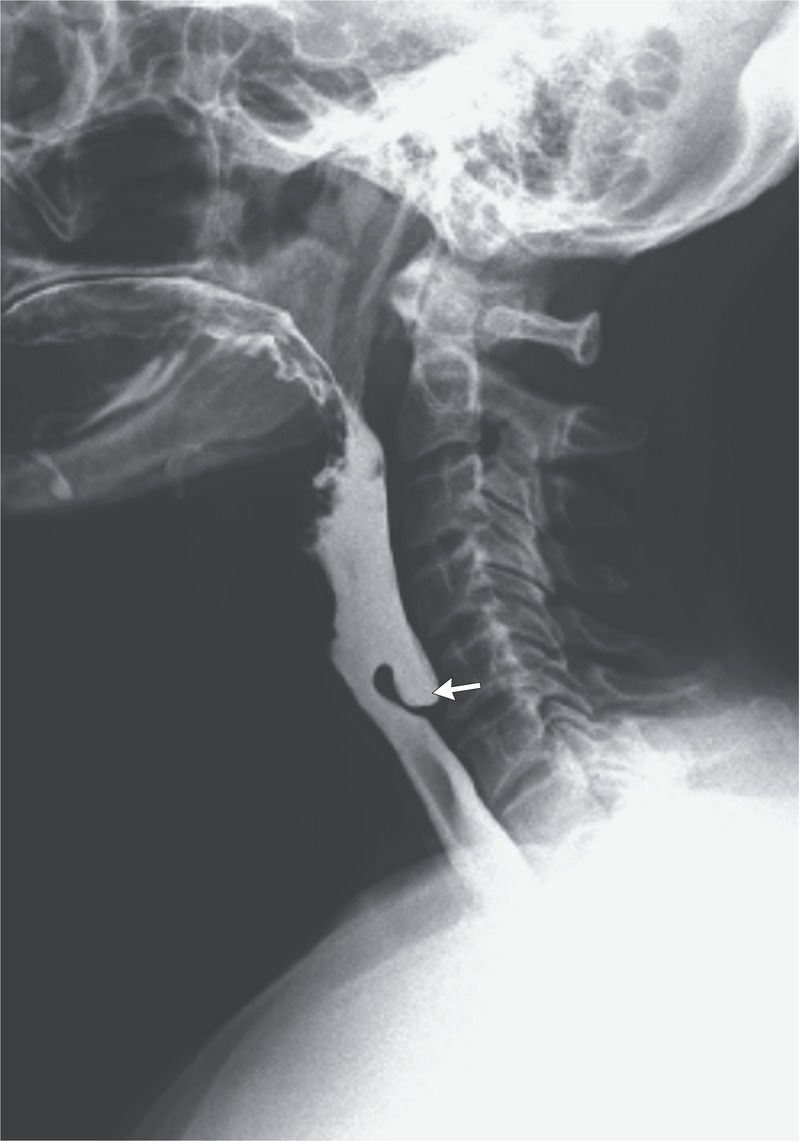

A 67-year-old man presented to the gastroenterology clinic with an 8-month history of progressive dysphagia, weight loss, regurgitation, and halitosis. A physical examination revealed no palpable cervical mass. Laboratory studies showed a moderately low serum albumin level. A barium swallow examination showed stasis of barium in the upper esophagus with an outpouching lesion anterior to the C5 and C6 vertebrae (arrow). Upper gastrointestinal endoscopy revealed a pharyngoesophageal diverticulum, or Zenker’s diverticulum. Zenker’s diverticula are herniations of the hypopharynx through a defect in Killian’s triangle, an area bound by the inferior pharyngeal constrictor muscles and cricopharyngeus muscles. These diverticula are thought to result, in part, from abnormalities of the upper esophageal sphincter. Small diverticula can be asymptomatic and left untreated, whereas large diverticula can result in dysphagia, regurgitation, chronic aspiration, or cough, and surgery may be warranted. In this patient, an endoscopic Zenker’s diverticulectomy was performed. Within 3 days after the surgery, the dysphagia, regurgitation, and halitosis had resolved, and the patient remained asymptomatic at a follow-up visit 8 months later.